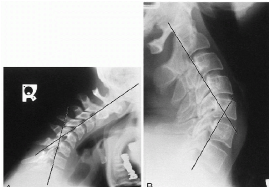

Q what is the name of this measurement? and what is the average + range?

A: George's Line

assesses the posterior surfaces of the vertebral bodies for a smooth vertical alignment. No average or range is specified.

A: Posterior Cervical Line

assesses for a smooth, arc-like curve of the spinolaminar junctions. No average or range is specified, but significance in children notes the C2 junction should not be more than 2 mm anterior to the line.